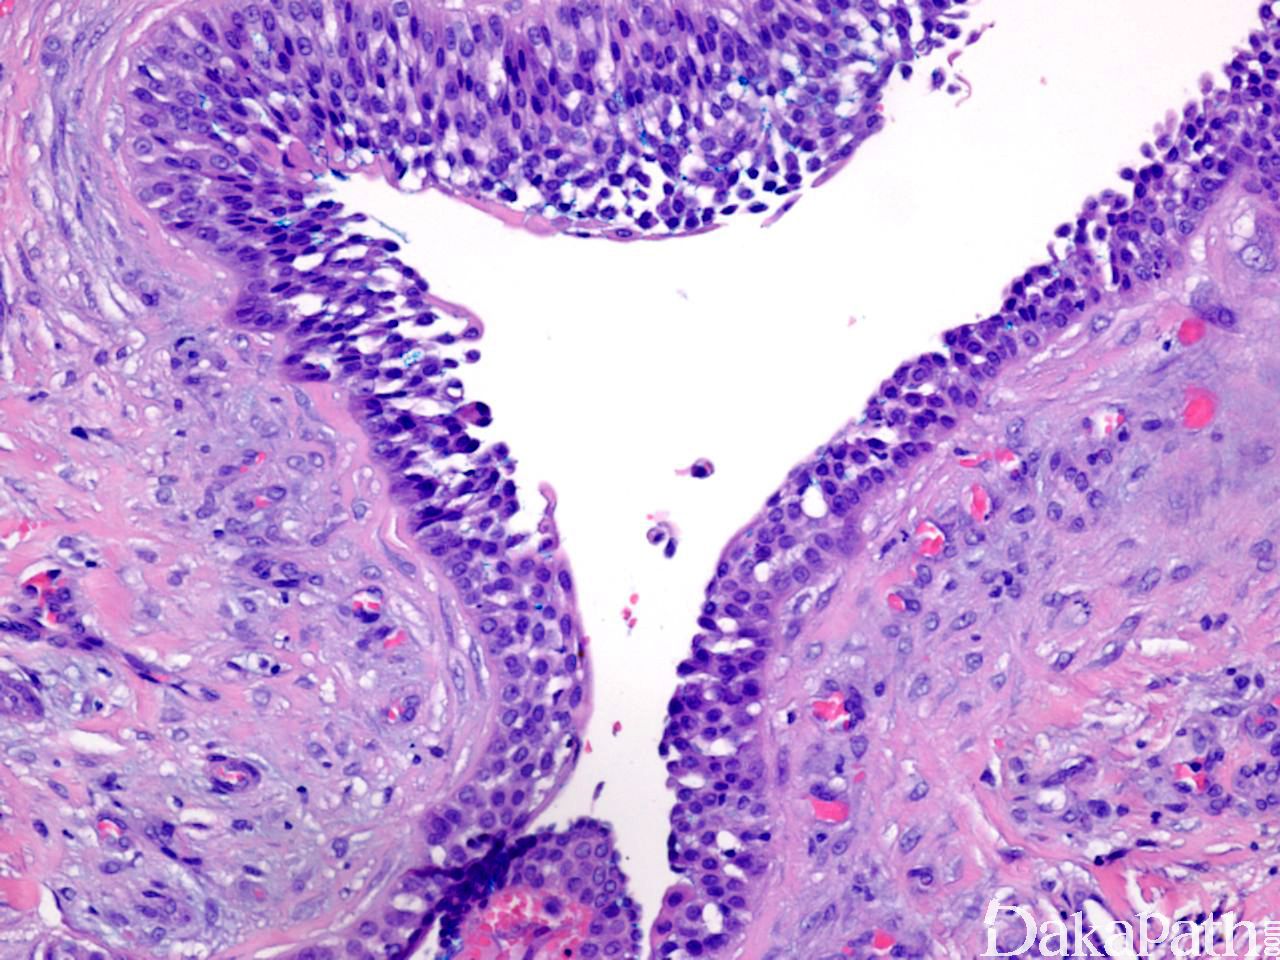

导管和囊性结构内衬立方形导管细胞或柱状分泌细胞,核形规则,染色质轻度增多,核分裂象少见;

某些区域可见鳞状分化,甚至角化珠形成;